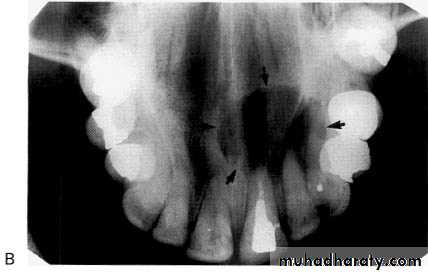

Nasopalatine duct/incisive canal cyst

This cyst develops from epithelial remnants of the nasopalatine duct or incisive canal.

• Site: Midline, anterior maxilla just posterior to the upper central incisors.

• Shape: — Round or oval (superimposition of the nasal septum or anterior nasal spine may cause the cyst to appear heart-shaped or resemble an inverted tear drop)

— Monolocular.

• Outline: — Smooth

—Well defined

—Well corticated (unless infected).

• Radiodensity: Uniformly radiolucent